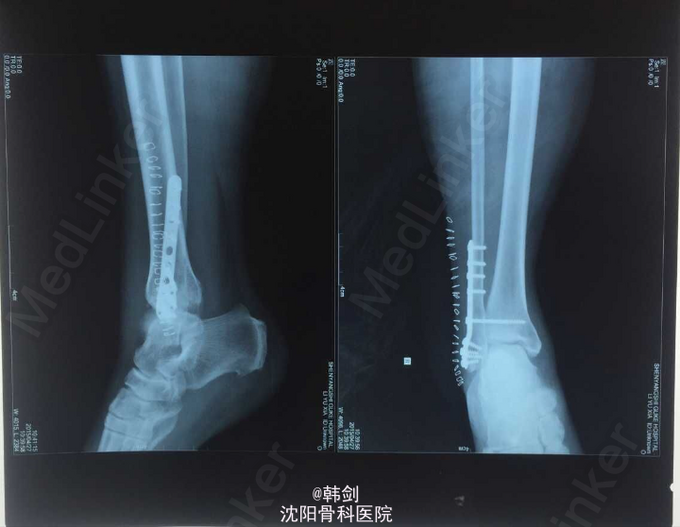

初步诊断:右外踝骨折伴胫距关节脱位。 确定诊断:右外踝骨折伴胫距关节脱位。 补充诊断:右后踝骨折。 处理:1手法复位效果不佳 2患者入院后9天行手术治疗

踝关节骨折大多数应追求精确的解剖复位及正常的关节间隙对位,才能最大程度的避免创伤性关节炎及关节功能障碍的发生可能及程度。提高患者远期的生活质量。